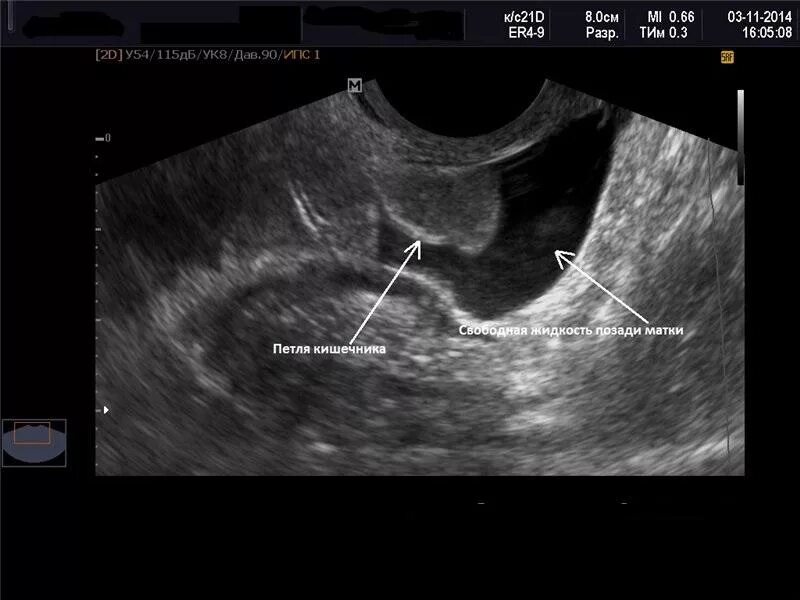

Жидкость в позадиматочном пространстве при беременности